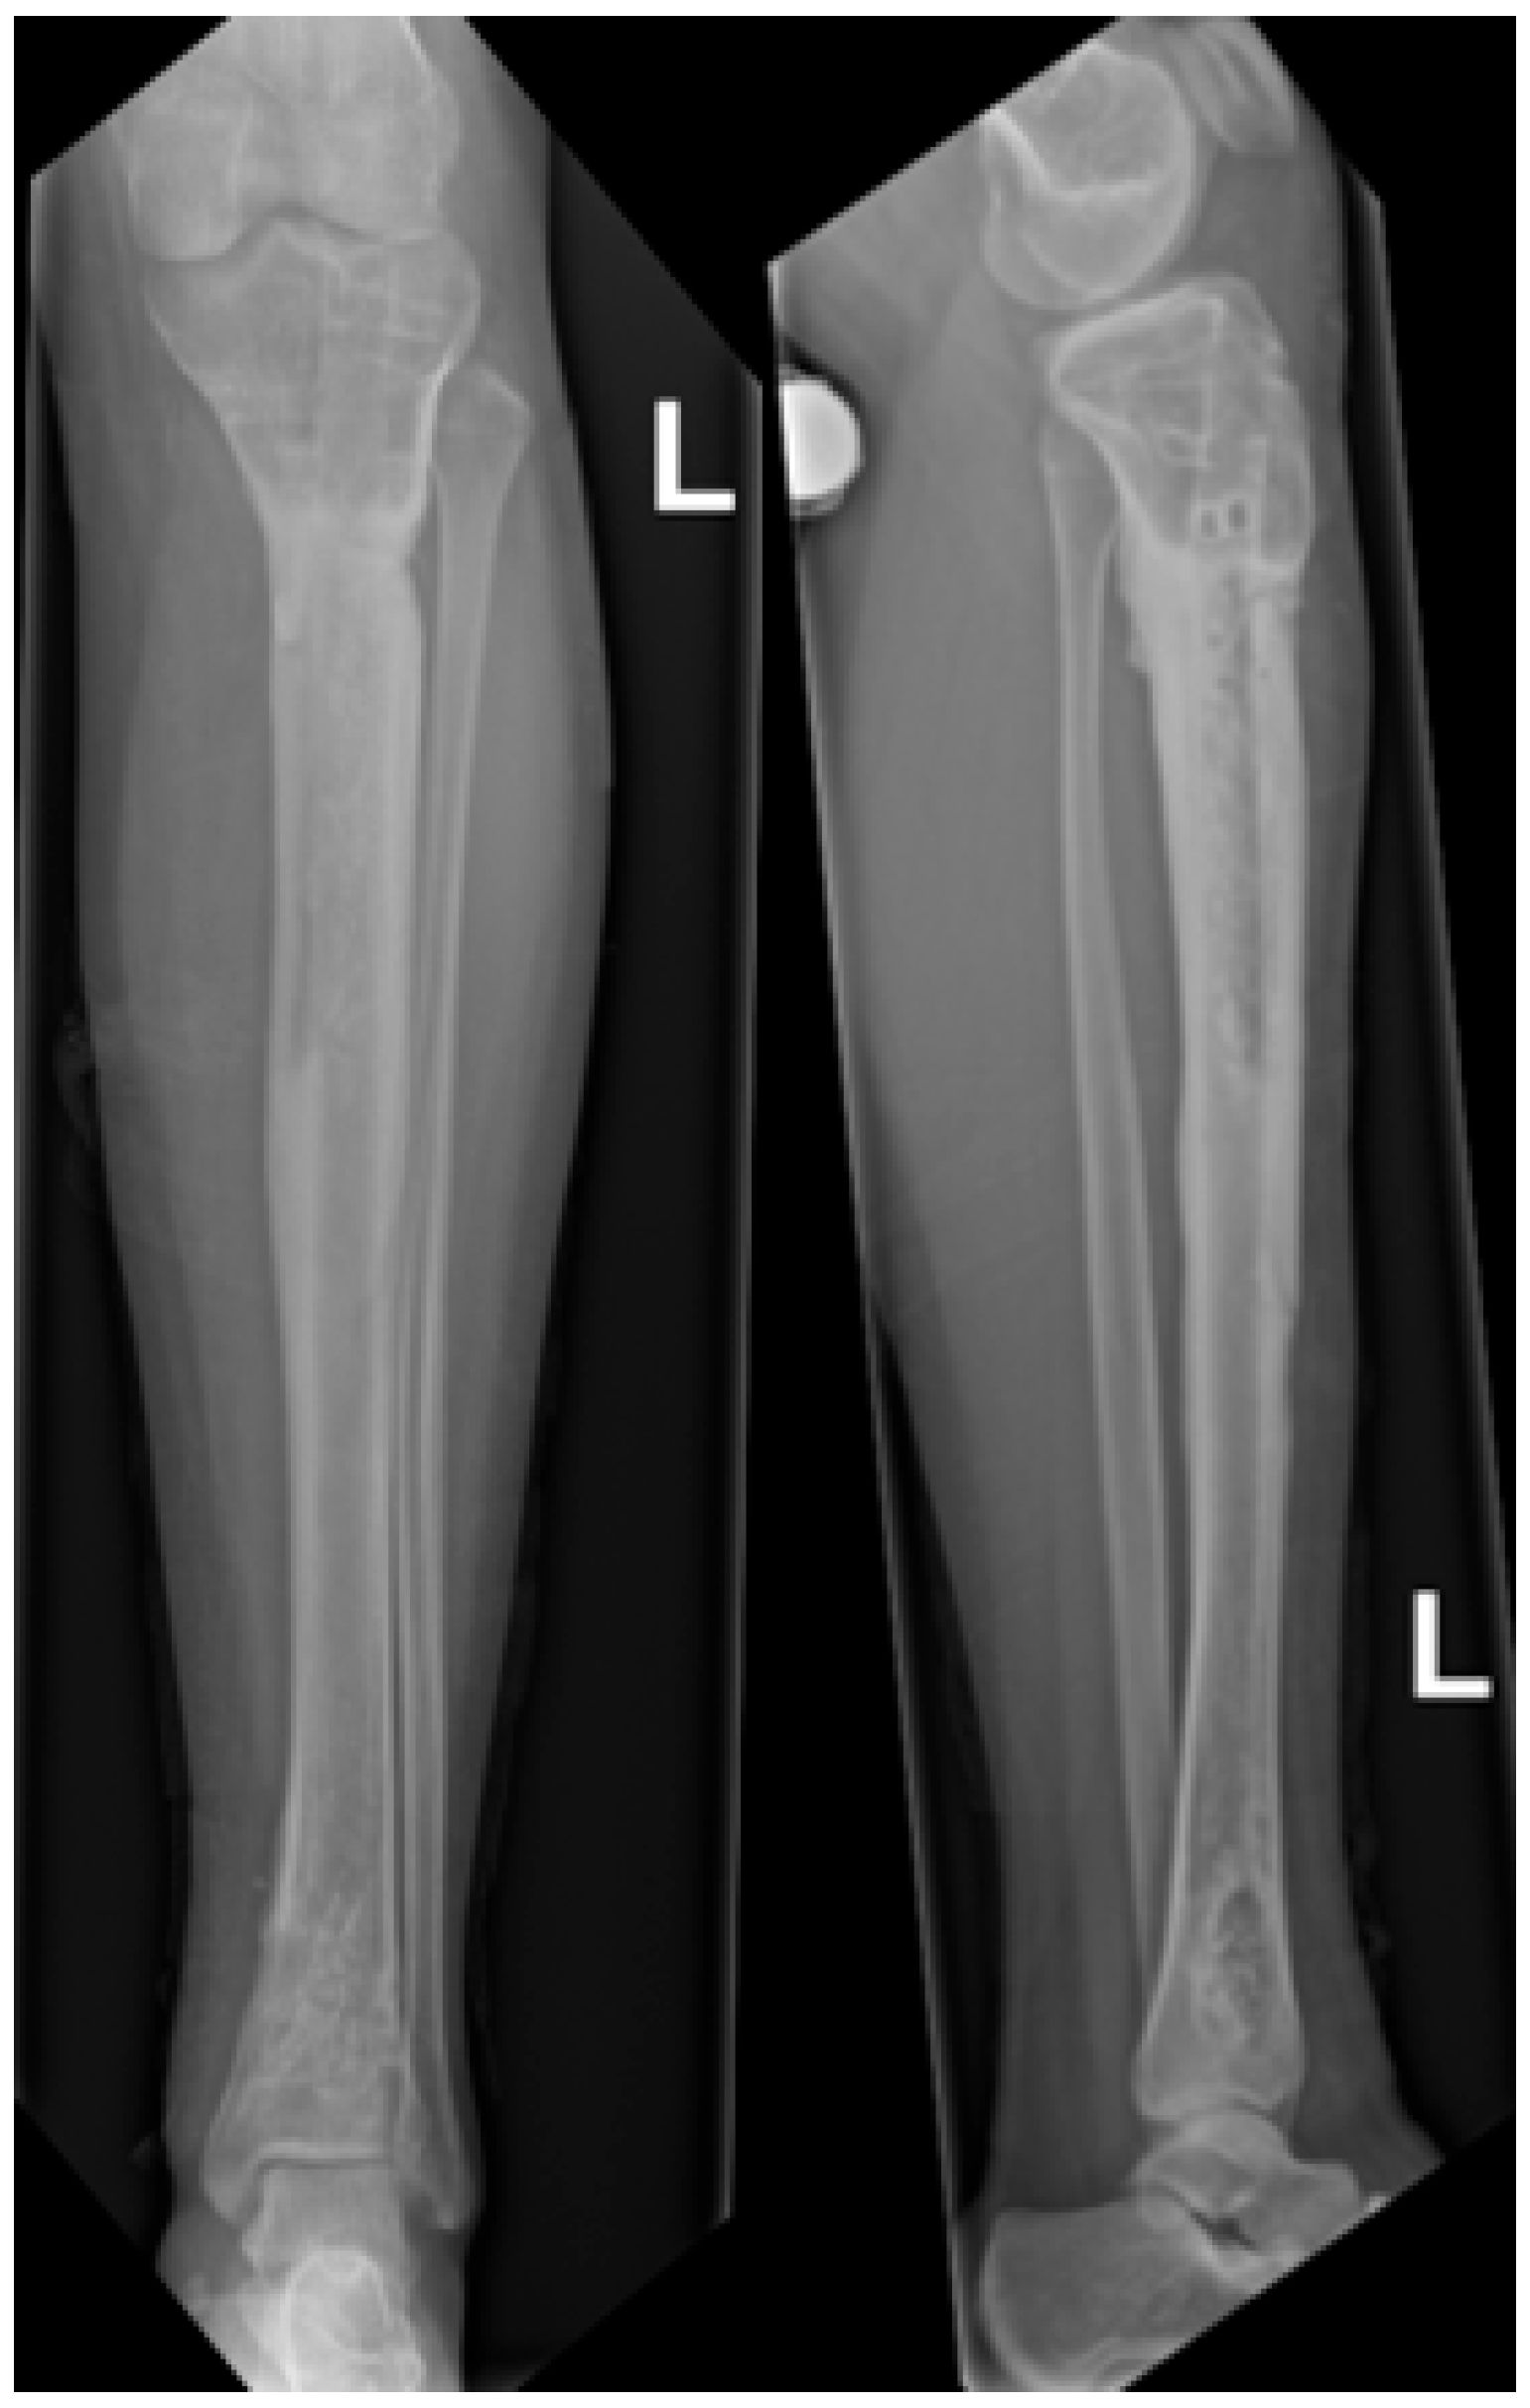

Figure 7.

Radiographs at 18 months follow-up showing anteroposterior view (left) and lateral view (right) of the tibia. Consolidation can be observed, demonstrated by bridging callus across cortices and the absence of visible fracture lines, with restoration of tibial alignment.

Figure 8.

Radiographs following hardware removal, showing anteroposterior view (left) and lateral view (right) of the tibia. Slight procurvatum and varus alignment are noted.